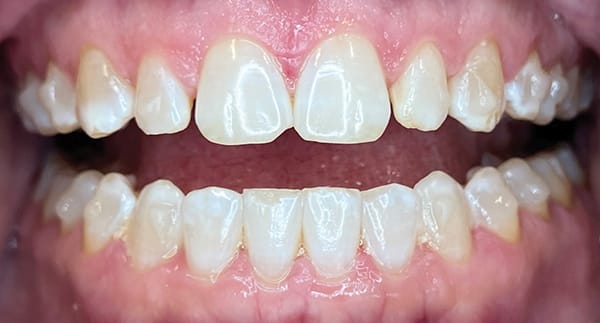

A 46-year-old female patient presented with the chief complaint of disliking the shape, color, and spacing of her front teeth. After conducting online research, the patient was adamant she did not want veneers or traditional bonding but instead preferred Bioclear® composite restorations (Bioclear, bioclearmatrix.com) on her maxillary and mandibular anterior teeth to preserve tooth structure. An intraoral scan using the iTero Element® 2 intraoral scanner (Align Technology, Inc, itero.com) and photographs were taken. It was discussed with the patient that prior to final restorations Invisalign® clear aligner therapy (Align Technology, Inc, invisalign.com) was needed to close all mandibular spacing (eliminating the need for restorations) and partially close the maxillary spacing (improving the height-to-width ratios of the final maxillary restorations). The patient completed Invisalign treatment in 15 weeks and then whitened with Opalescence™ PF 10% whitening gel (Ultradent, ultradent.com). An intraoral scan with the iTero Element 2 scanner was taken for a pre-prosthetic lab wax-up of teeth Nos. 6 through 11. These teeth were restored with full esthetic composite veneers using the Bioclear heated composite injection overmolding technique with Filtek™ Supreme Ultra Universal Restorative White Body paste and flowable (3M Oral Care, 3m.com). No tooth structure was resected. The patient was immediately scanned for Vivera® retainers. She was thrilled with her smile transformation.

Direct composite restorations with the Bioclear method

are minimally invasive, additive, and esthetically natural looking.